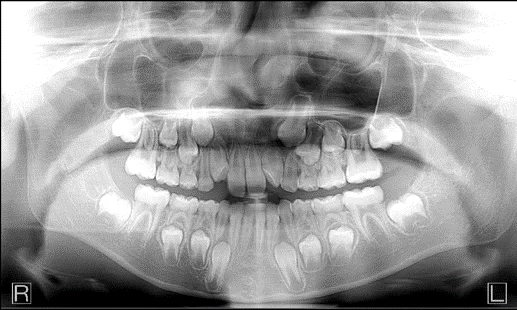

Not only Bitewings, but an entire FMX!

Vertical bitewing feature as well as FMX Clipping feature creates 18 intraoral-sized images clipped from the pan with one click.

Ideal tool for patients who won’t tolerate traditional PAs

- Instead of taking 18 individual images with an intraoral X-Ray, they can all be generated at once in 14 seconds.

See the FMX Clipping In Action!

“A very elegant solution for a full mouth series with a simple extra oral scan.” — Dr. Salim Shafi, Phoenix, AZ